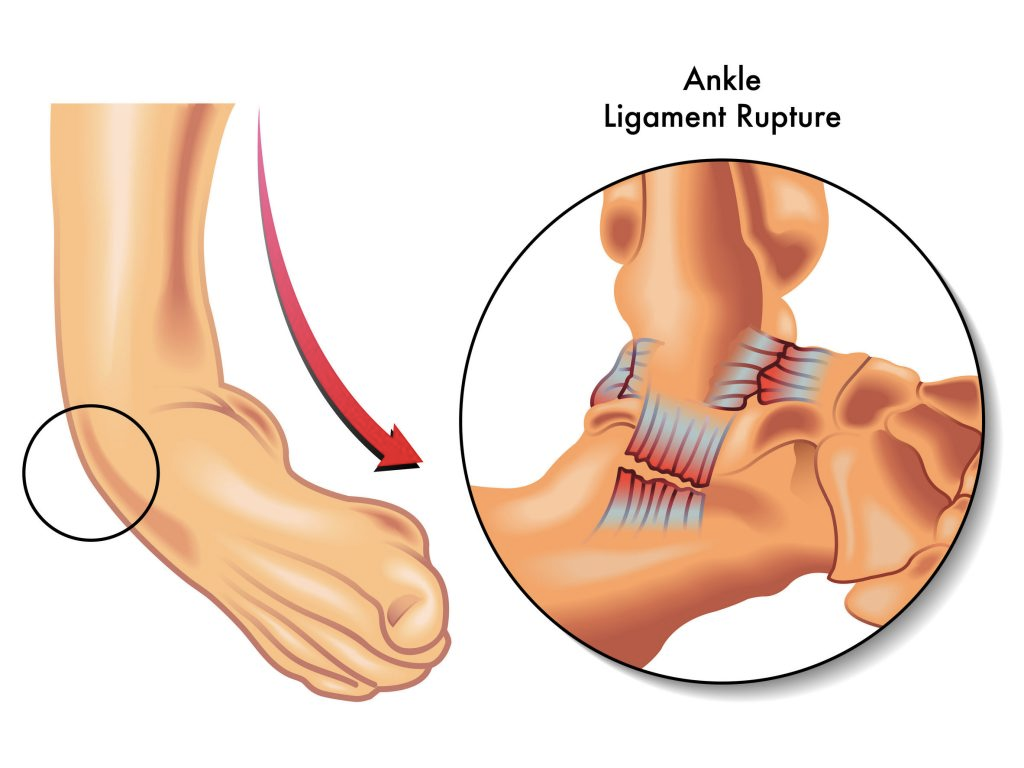

No momento da entorse, os ligamentos que estabilizam o tornozelo são estirados ou rompidos por um movimento brusco. 85% das lesões ocorrem em inversão, ou seja, a sola do pé é projetada para o centro do corpo, comprometendo o complexo de ligamentos laterais.

A entorse de tornozelo ocorre quando há um movimento súbito e anormal da articulação, levando ao estiramento ou, em casos de maior gravidade, ruptura dos ligamentos que estabilizam a junta.

Tanto os ligamentos da face lateral quanto medial do tornozelo podem ser acometidos. Mas o complexo ligamentar lateral, comumente, é o mais lesionado. O paciente quando se recorda da lesão normalmente descreve um movimento abrupto do pé em inversão, flexão plantar e rotação interna, podendo ser acompanhada de um estalido perceptível e/ou audível. Seguido de dor, edema e incapacidade funcional, ou seja, impossibilidade de manter o pé apoiado.